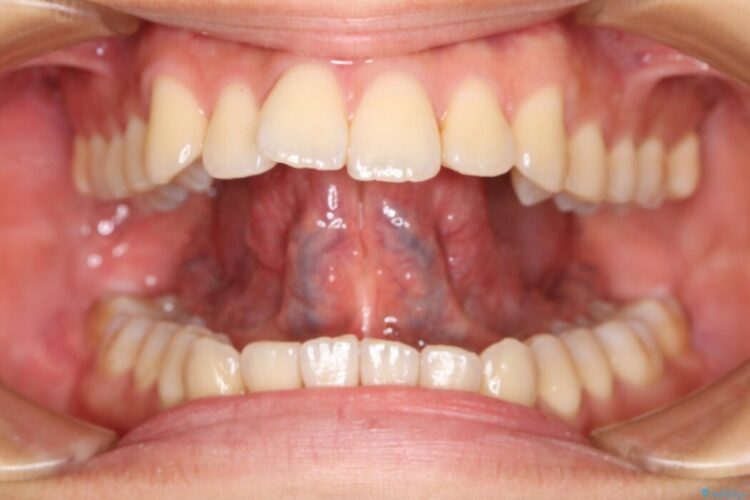

舌小帯は舌の下面についているヒダのことを指します。個人によっても違いますが、舌小帯が短い・硬い場合は舌の動きが制限されてしまいます。それによって滑舌の悪さ、摂食・嚥下に影響を及ぼすことがあります。

このような舌小帯の異常の場合、「舌小帯切除術」を行うことがあります。

本症例ではレーザー機器を用いて手術を行いました。これにより従来のメスを使用する術式と比べて所要時間の短縮が図れ、かつ縫合を必要としないため術後の不快感も軽減することができます。